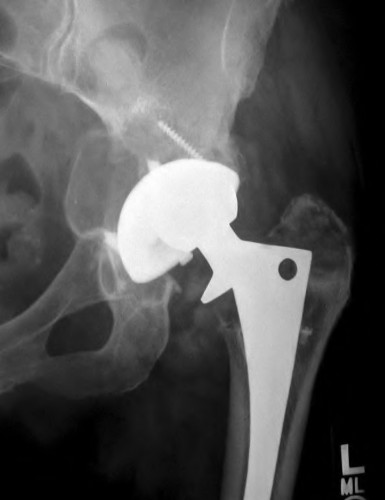

Question 68

A 78-year-old female sustains a periprosthetic femur fracture 10 years after a cemented THA. Radiographs show a fracture around the tip of the stem with a loose femoral component and poor proximal bone stock, but adequate diaphyseal bone.

What is the most appropriate surgical treatment?

Explanation